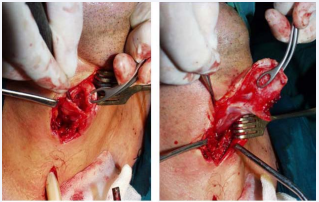

The first incision extends from lower middle of the hyoid bone to the incisura thyroid. Flap pedicle is in the side of involved hemyglottis. Rectangular flap is prepared in front of intact hemyglottis. The width of the flap is only 7-8 mm, the height is between incisura thyroid and thyroid cartilage bottom. The third vertical incision extends between the lower middle tip of the thyroid and the lower middle tip of the cricoid. Laryngofissure with median thyrotomy is performed in Figure (4).

Figure 4 (a) Laterally pedicle flap, (b) Laryngofissure with median thyrotomy

Figure 4: (a) Laterally pedicle flap, (b) Laryngofissure with median thyrotomy